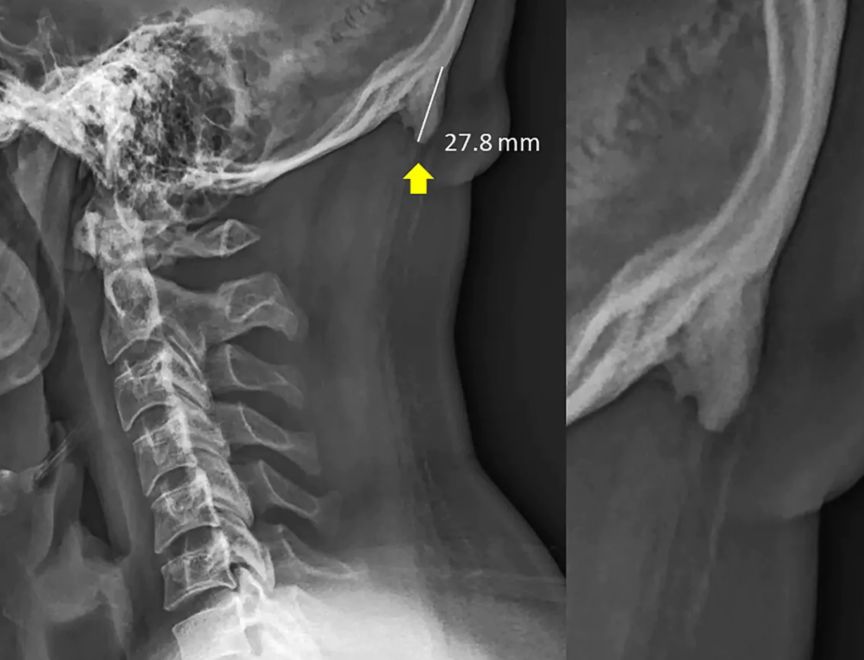

“关注啦!关注啦!看手机看多了,脑袋后面可能会长角!”

这个研究来自澳大利亚阳光海岸大学的一个医生,David Shahar。他在过去20年从医的经历中,发现越来越多的人,在后脑勺窝里、颈子上面的地方,出现了一个小小的凸起。这玩意儿,学名为“枕外隆凸”(external occipital protuberance)。他发现了这个现象之后,和同事一起“看了各个年龄的1200多张X光片”,发现在18-30岁的人中,这块小骨头出现的频率“异常高”。最大的一个枕外隆突案例,“角”甚至凸出来了接近3厘米。

然后,判定长出枕骨隆突(原 paper 根本没说“长角”,毕竟动物的角和骨骼的成分根本不同)的标准在10毫米,只要超过这个值,就在数据中算作是阳性,而不一定真的长“出来”了那个东西,文中配图里的案例其实非常极端。研究者把这些X光片按年龄和性别分了组,发现年轻人当中长出枕骨隆突的人要多一点点:35%的30岁以下的年轻男性有这个隆突,而在30-50岁的观察者中,此比例不到15%。